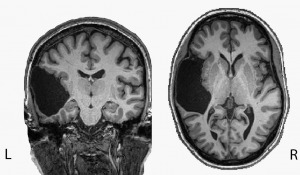

这个微分方程可以用来模拟神经元间通过突触的相互作用方式,换言之就是大脑传递信息的过程。现实生活中有诸多应用场景,比如自动驾驶、大脑和心脏的监测等。

这次MIT的突破,在于找到了两个神经元之间通过突触相互作用微分方程的近似解析解。

突触,即一个神经元的冲动传到另一个神经元或另一细胞间的相互接触的结构。两个神经元之间神经冲动,则是由突触前末梢,传递给突触后神经元的。

要模拟神经元间通过突触相互作用的过程,就需要模拟传导的动作电位。

希望通过测量数百万个神经元连接,建立大脑动力学模型。

一旦我们对神经元和突触的联系有了一个解析解描述,我们就可以用数十亿个细胞建立大脑的计算模型了。

据神经学家估计,人脑神经元数量在1000亿个左右,不知道团队是否会挑战“模拟人类大脑”这一难题(手动狗头)。